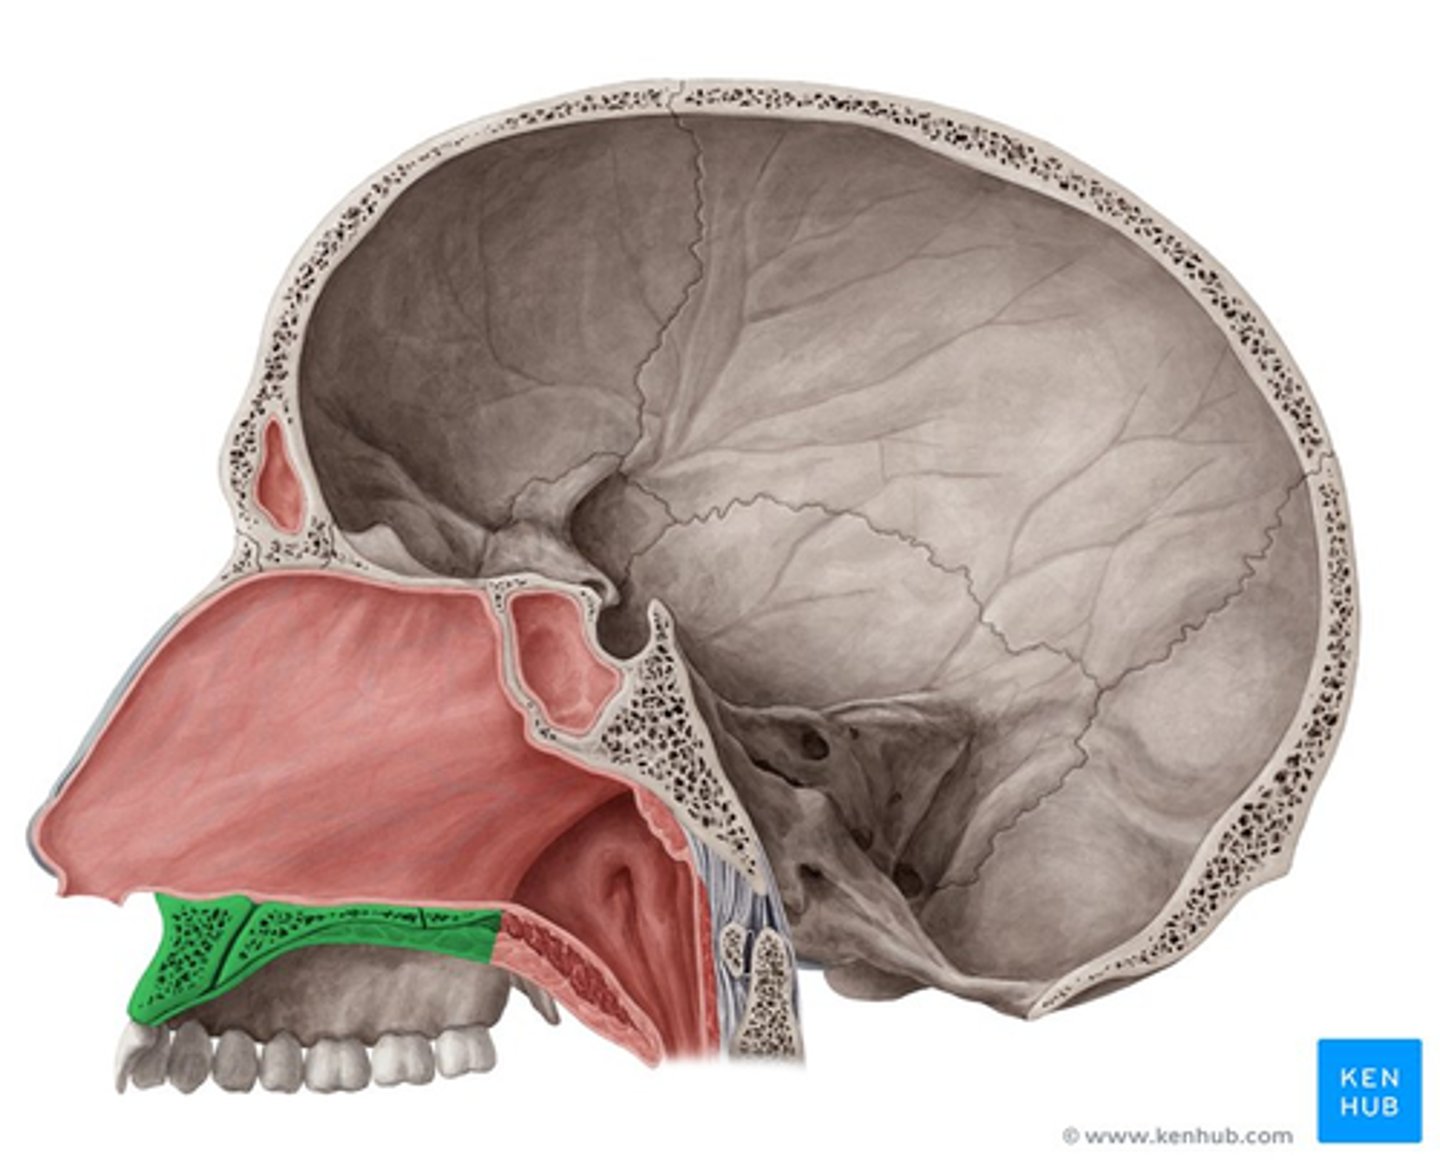

hard palate

palatine bone (horizontal plate)

maxilla (palatine process)